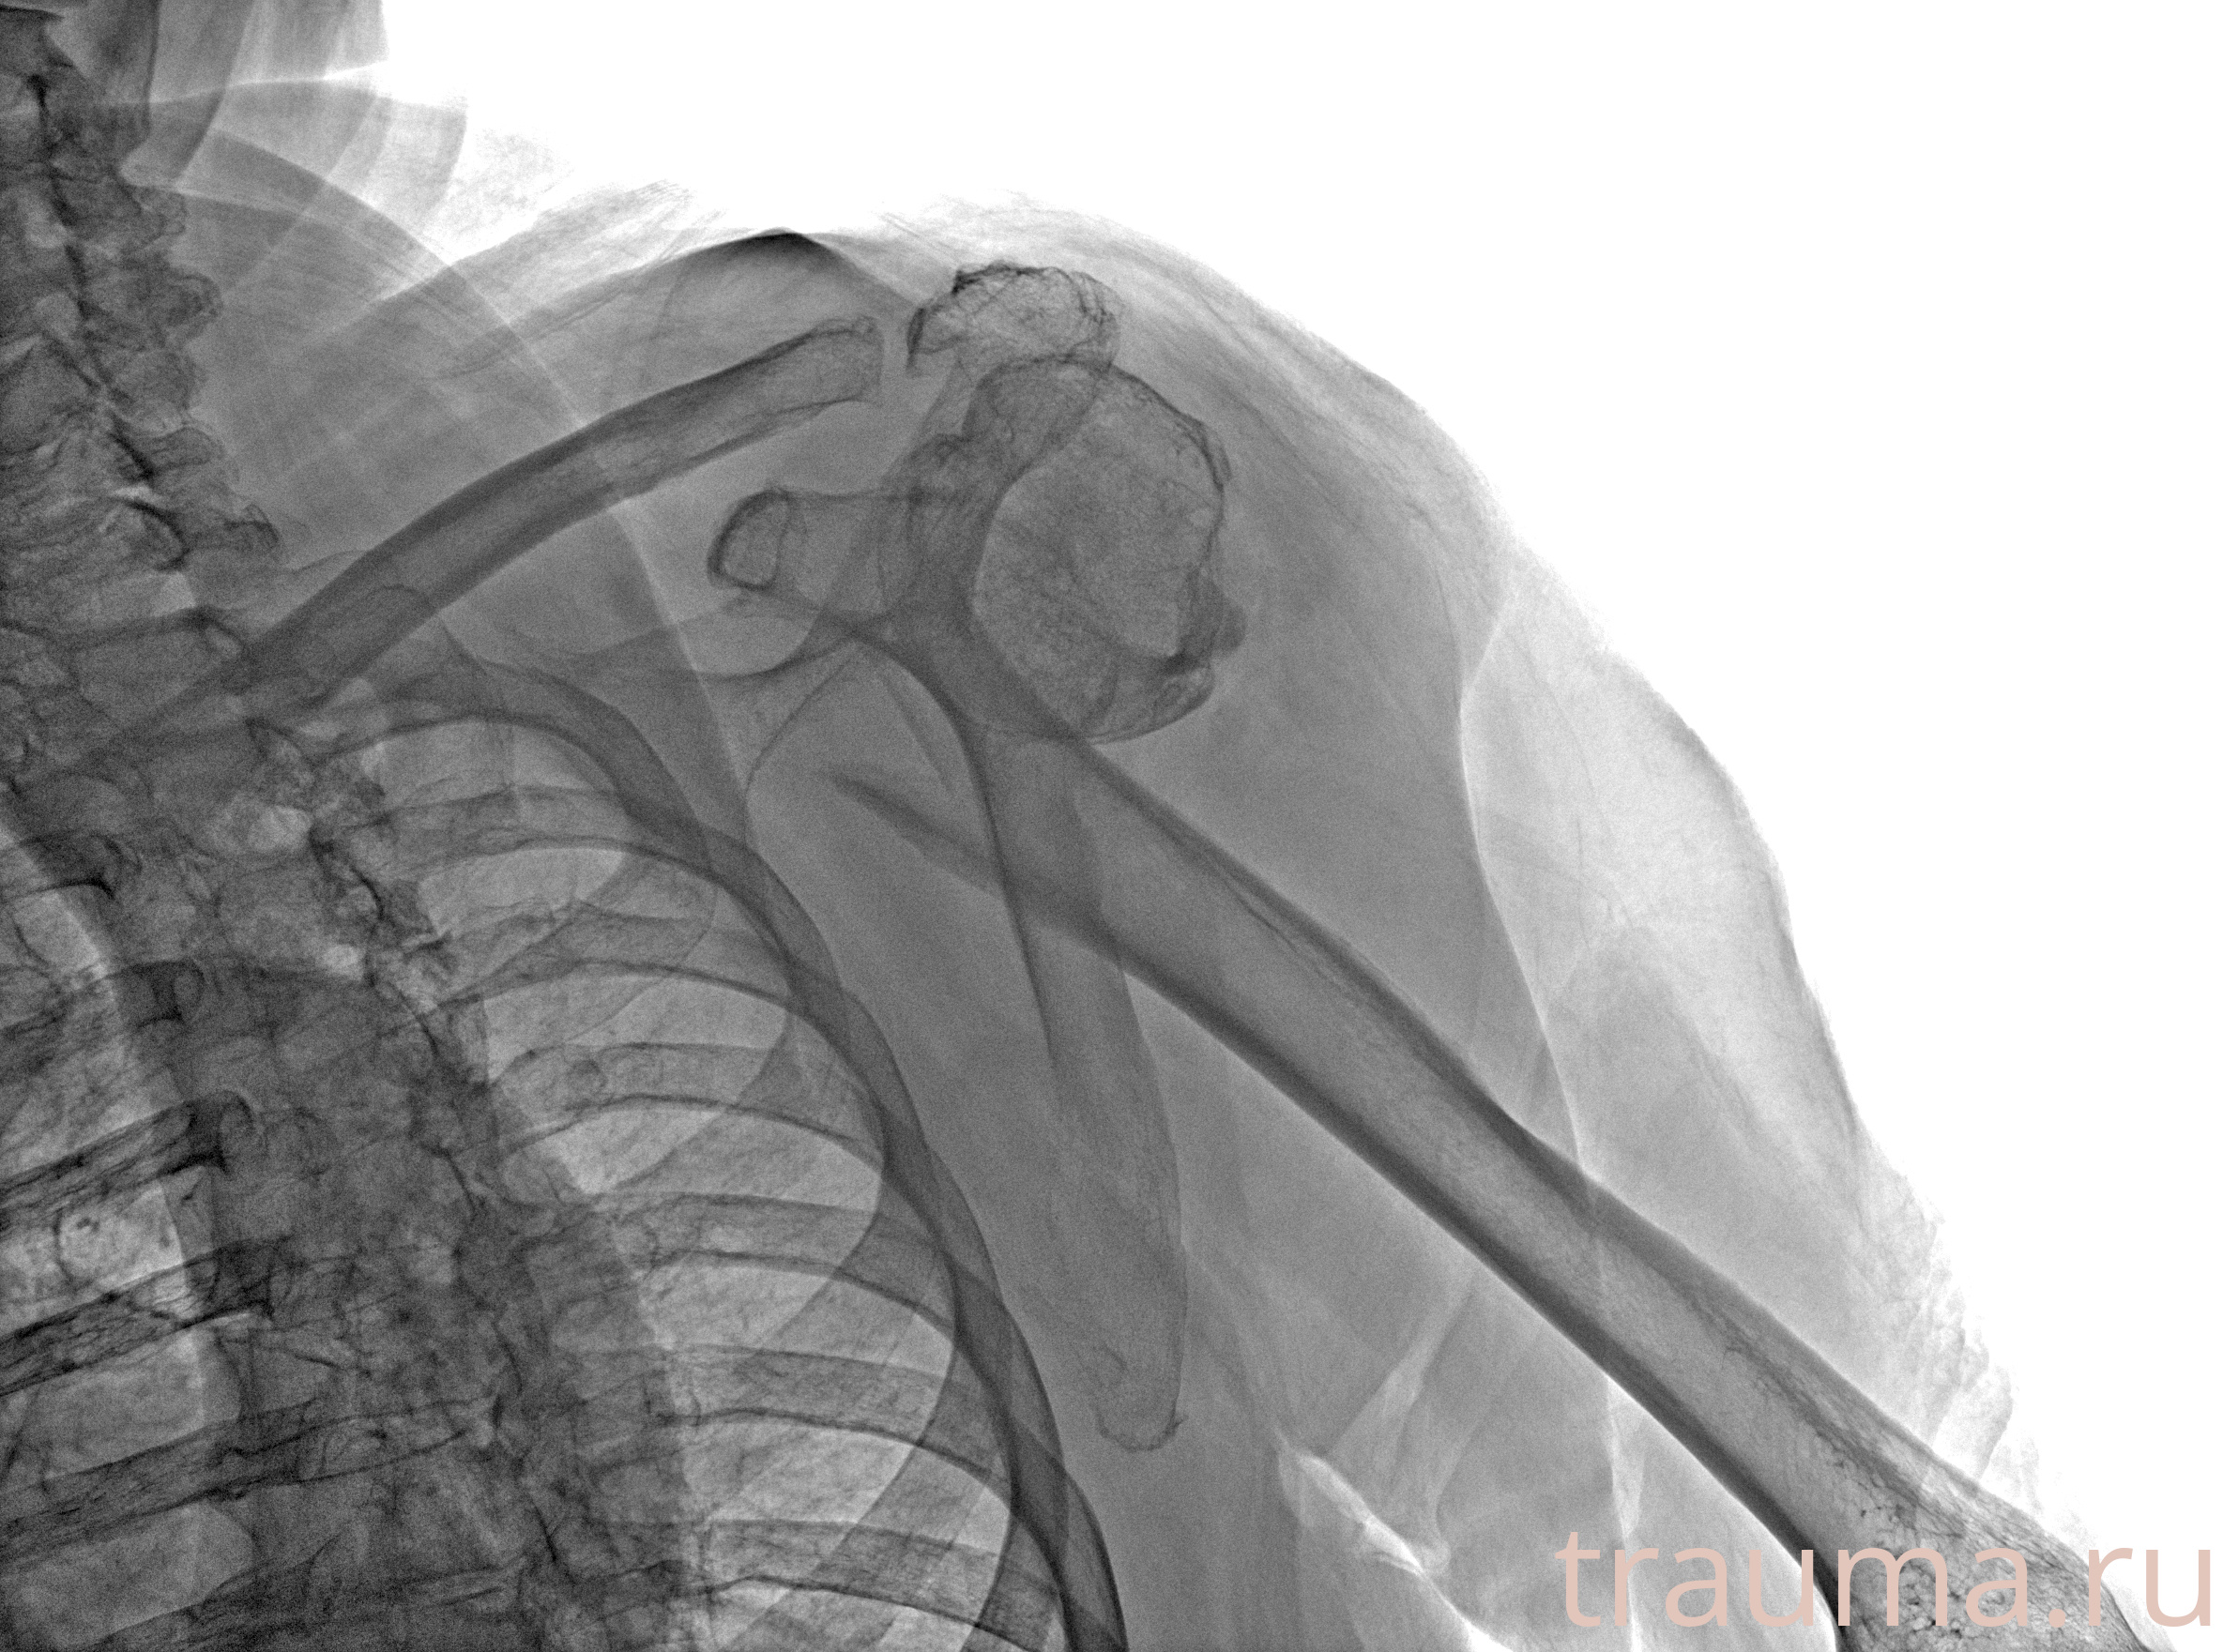

Рентгенограммы

Рентген на дому: по вашему адресу приезжает врач-рентгенолог, травматолог-ортопед с мобильным рентгеновским аппаратом, проводит диагностику травмы или заболевания, делает необходимые рентгенограммы, дает рекомендации по дальнейшему лечению. Получить качественные снимки в домашних условиях возможно благодаря уникальной методике, разработанной МосРентген Центром для института  Склифосовского